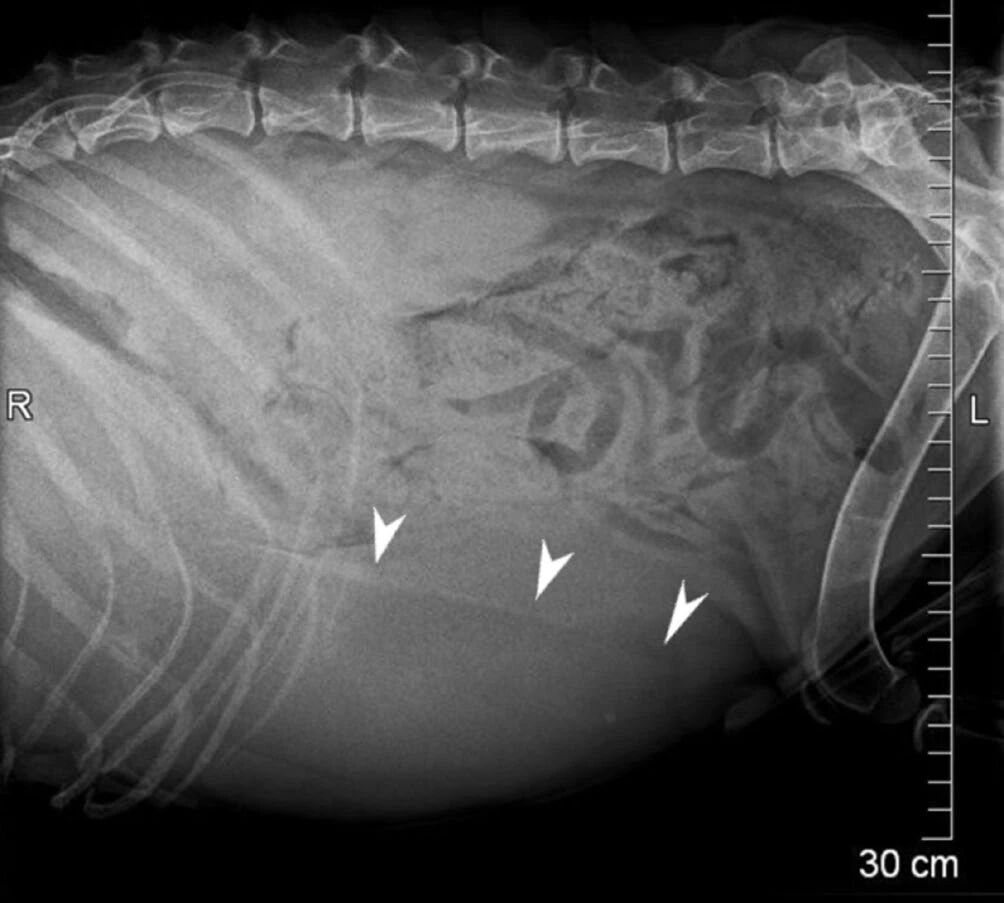

因体重下降和肝肿大而转诊。既往检查提示肝肿大(下图)。

↑ 侧面X光影像,可见明显的肝肿大(肝脏轮廓用箭头标出)。